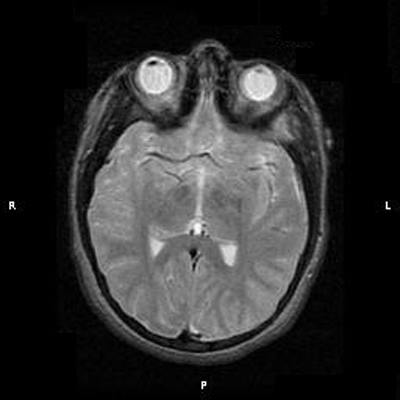

Clinical information: The patient was a 13 year-old girl who presented with worsening headache and some difficulties with memory, concentration and attention. MRI studies disclosed a 2.1 x 1.9 x 1.8 cm enhancing mass in the left temporal bone and sphenoid wing. The mass extended intracranially and abuts the left temporal bone accompanied by dural enhancement at that location. There is also extension through the bone into the submuscular temporal region. The following photos are taken from representative regions of the lesion. Panel 1 and 2 are CT scans at soft tissue and bone density respectively. Panel 3 and 4 are T1 weighed images without and with contrast respectively. Pandl 5 is proton density image. Panel A to D are cytologic (squash) prepartion for intra-operative consultation. Panel E and F are frozen sections for intraoperative consultation. Panel G to L are paraffin embedded sections.

| 1. | 2. | 3. | 4. | 5. |